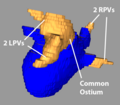

- Carma 3RPV.png 600 × 555; 148 KB

- Carma 3RPVs.png 600 × 555; 148 KB

- Carma Com LPV.png 599 × 524; 122 KB

- Carma Norm LPVs.png 651 × 631; 138 KB

- Carma Norm RPVs.png 593 × 551; 115 KB